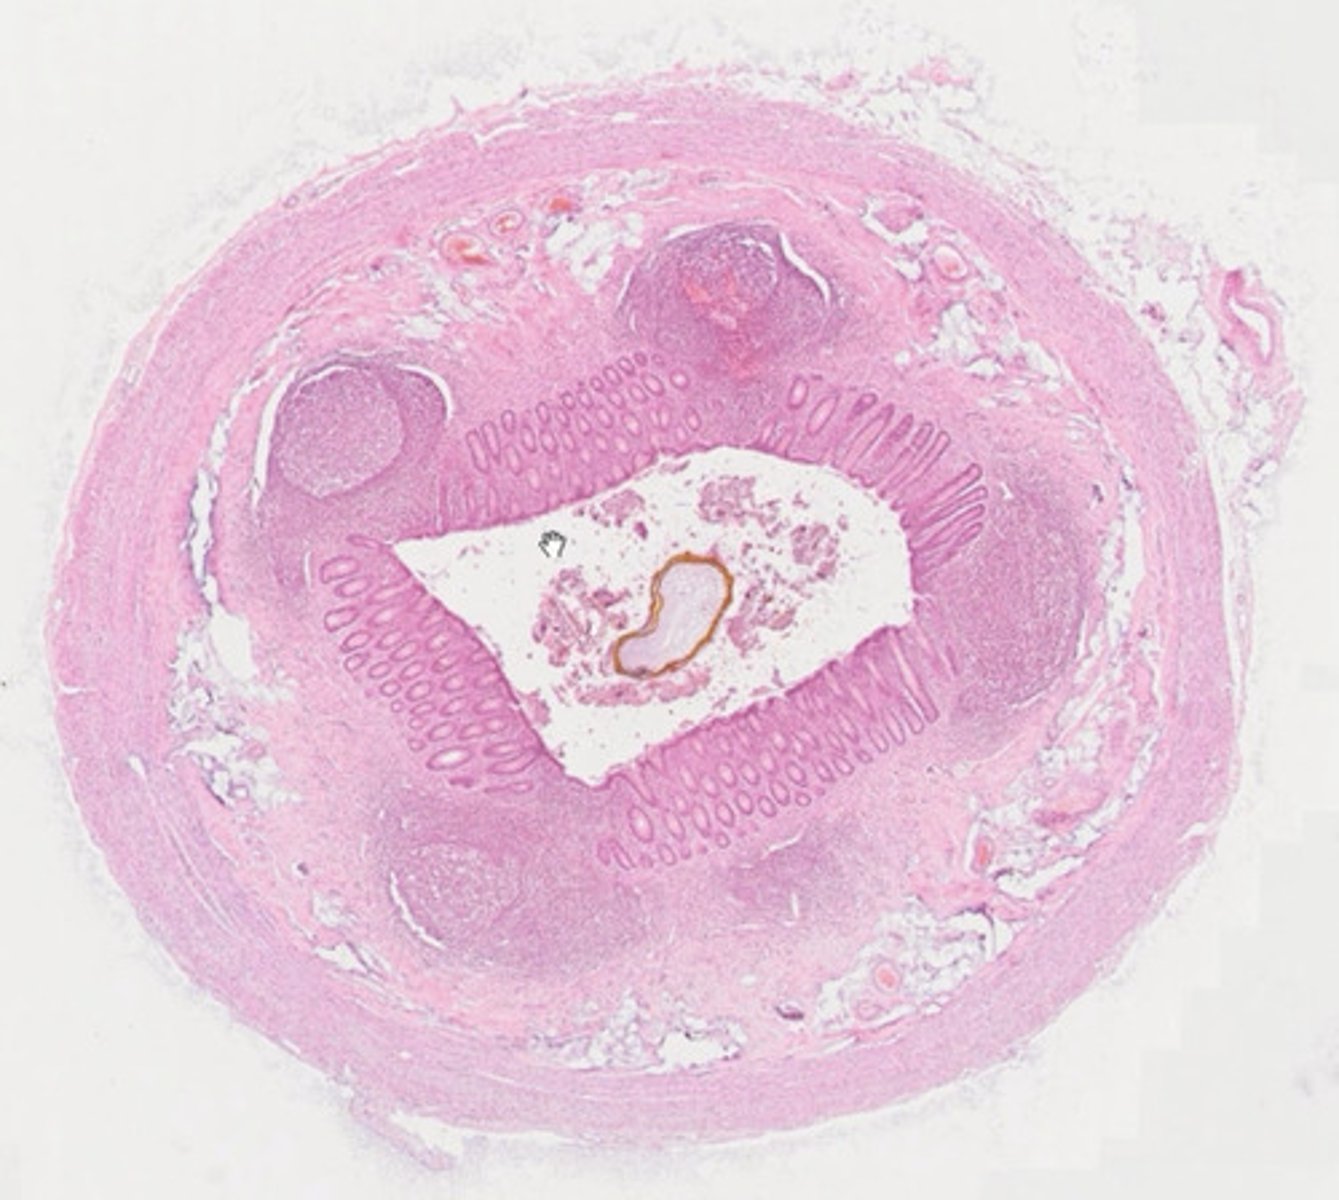

Moczowód (H+E)